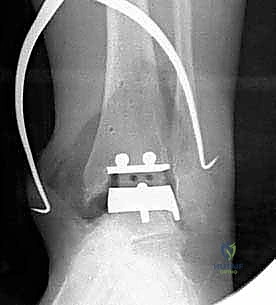

تتكون غرسة STAR من ثلاثة أجزاء رئيسية ولا تستخدم الأسمنت العظمي (Cementless)، بل تعتمد على النمو العظمي الدقيق داخل مسام الغرسة لتثبيتها بشكل دائم:

- المكون الظنبوبي (Tibial Component): صفيحة معدنية مسطحة من سبائك الكوبالت والكروم (Cobalt-Chromium)، تُثبت في أسفل عظمة الساق (الظنبوب) بواسطة أسطوانتين معدنيتين تدخلان في العظم لضمان الثبات المطلق.

- المكون الكاحلي (Talar Component): قطعة معدنية تغطي قبة عظم الكاحل، مصممة بشكل تشريحي منحني يحاكي تماماً شكل العظمة الأصلية، وتحتوي على أخدود طولي.

- الحشوة البلاستيكية المتحركة (Mobile Polyethylene Bearing): هذا هو سر نجاح غرسة STAR. هي قطعة من البلاستيك الطبي عالي الكثافة (UHMWPE) توضع بين القطعتين المعدنيتين. هذه القطعة ليست ثابتة، بل تنزلق بحرية للأمام والخلف، وتسمح بدرجة طفيفة من الدوران. هذا التصميم "المتحرك" يقلل بشكل هائل من إجهاد القص (Shear Stress) على واجهة العظم والمعدن، مما يقلل من احتمالية تخلخل الغرسة (Loosening) على المدى الطويل، ويمنح المريض نطاق حركة فسيولوجي مذهل.

تعتمد دقة الجراحة على المحاذاة الصحيحة. يتم استخدام أجهزة توجيه متطورة (Jigs) تثبت على عظمة الساق باستخدام دبابيس معدنية. يتم التحقق من صحة الزوايا والمحاور باستخدام جهاز الأشعة السينية المباشر داخل غرفة العمليات (C-arm Fluoroscopy). يضمن الدكتور هطيف أن يكون القطع موازياً للأرض تماماً عند وقوف المريض.